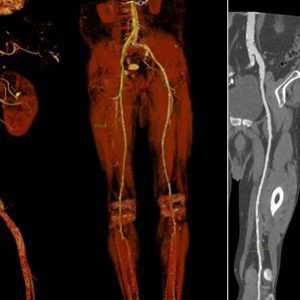

КТ-ангиография сосудов брюшной полости

КТ-ангиография сосудов брюшной полости считается одним из наиболее современных методов определения состояния здоровья сосудистой системы в указанной области. Его главным отличием выступает привлечение специального контрастного вещества.

Обычное ультразвуковое исследование не способно предоставить развернутую картину по структуре и общему состоянию сосудов в брюшной области, что способствовало разработке и внедрению технологии ангиографии. Вместе с контрастом получается визуализировать абсолютно все участки сосудистого русла. На основе полученной визуализации доктор сможет определить не только строение больших и мелких сосудов, но также выявить возможные аномалии в близлежащих органах.

Детализированная картина помогает обнаружить даже малейшие просветы, либо выявить внутренние образования, будь то онкологические опухоли или обычные тромбы. Причем изображение настолько подробно, что опытный рентгенолог способен на его основе распознать только-только зарождающиеся заболевания. Особенно актуален поиск недугов на начальной стадии развития для онкологических заболеваний.

Ангиография нижних конечностей

Почти у каждого третьего человека в возрасте старше 65 лет имеется заболевание артерий или вен нижних конечностей. Также усугубляют данную патологию курение и сахарный диабет в анамнезе. Основной признак недугов артерий нижних конечностей — это болезненность в ногах при длительной ходьбе, возникающая в разных местах, что зависит от уровня поражения сосудов.

Итак, в каких случаях проводится ангиография сосудов нижних конечностей:

- Облитерирующий атеросклероз и эндартериит сосудов нижних конечностей;

- Тромбоз глубоких вен;

- Тромбофлебит поверхностных вен нижних конечностей;

- ряд других патологических состояний.